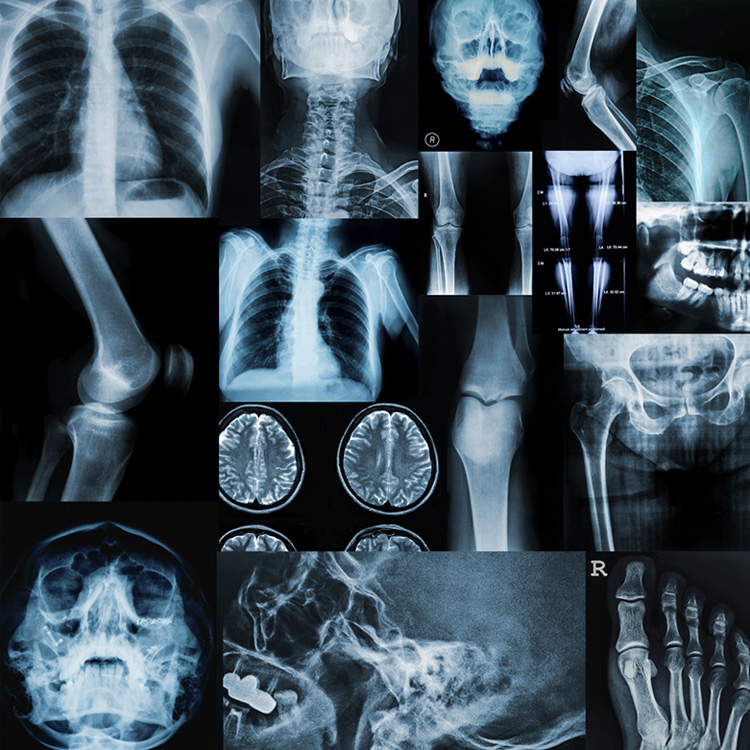

TUTTO QUELLO CHE C’È DA SAPERE SUGLI ESAMI RADIOLOGICI

Cosa sono i raggi X?

I raggi X sono radiazioni in grado di attraversare il corpo umano e consentono di realizzare immagini che riproducono le strutture anatomiche.

Indagini che impiegano raggi X

• Radiografia convenzionale

• TC/TAC

• Mammografia

• Radiografia odontoiatrica (ortopantomografia, radiografia endorale)

• Densitometria ossea

• Procedure di radiologia interventistica con immagini che guidano il medico nell’intervento (es. coronarografia, studi angiografici)